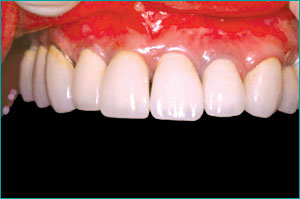

非常にきれいな状態を回復できる。

インプラントとセラミックの歯を入れる。